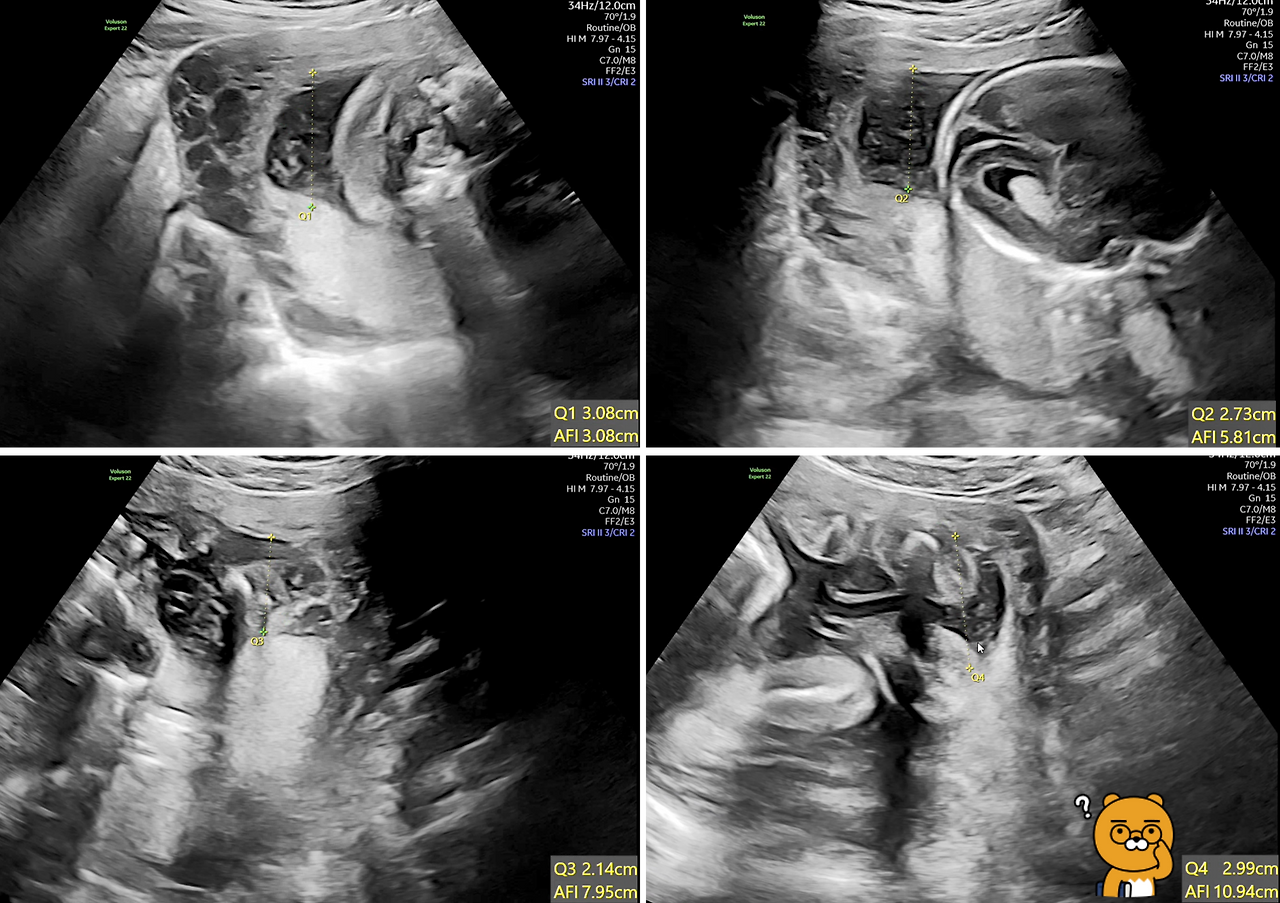

양수 양을 측정하는 방식에는 SDP(SIngle Deepest Pocket)과 AFI(Amniotic Fluid index, 양수지수) 이렇게 두 가지 방식이 있는데 제가 보기에는 AFI(양수지수) 방식을 사용한 것 같습니다. 이 방식은 배꼽을 기준으로 4군데에서 양수 깊이를 측정하는데 정상값은 5㎝이상~24㎝미만이라고 합니다.

딸 애의 경우 7.9cm이니 정상값이긴 하지만 8cm 미만이면 조기분만의 위험이 있어 자주 검사를 해야 한다고 하네요. 그런데 아래 제가 딸 애의 초음파 사진을 보니 Q1+Q2+Q3+Q4=10.94㎝로 나오는데 좀 헷갈리네요. 각 Q 포인트를 찍을 때마다 AFI 값이 합쳐지고, 최종 Q4의 AFI 값은 Q1~Q4까지의 수치를 합친 것이니까 10.94㎝가 맞거던요.

딸 애와 아내가 잘못 들은 것인지 아니면, 의사분이 잘못 말씀하신 것인지 잘 모르겠네요.

AFI 초음파.png